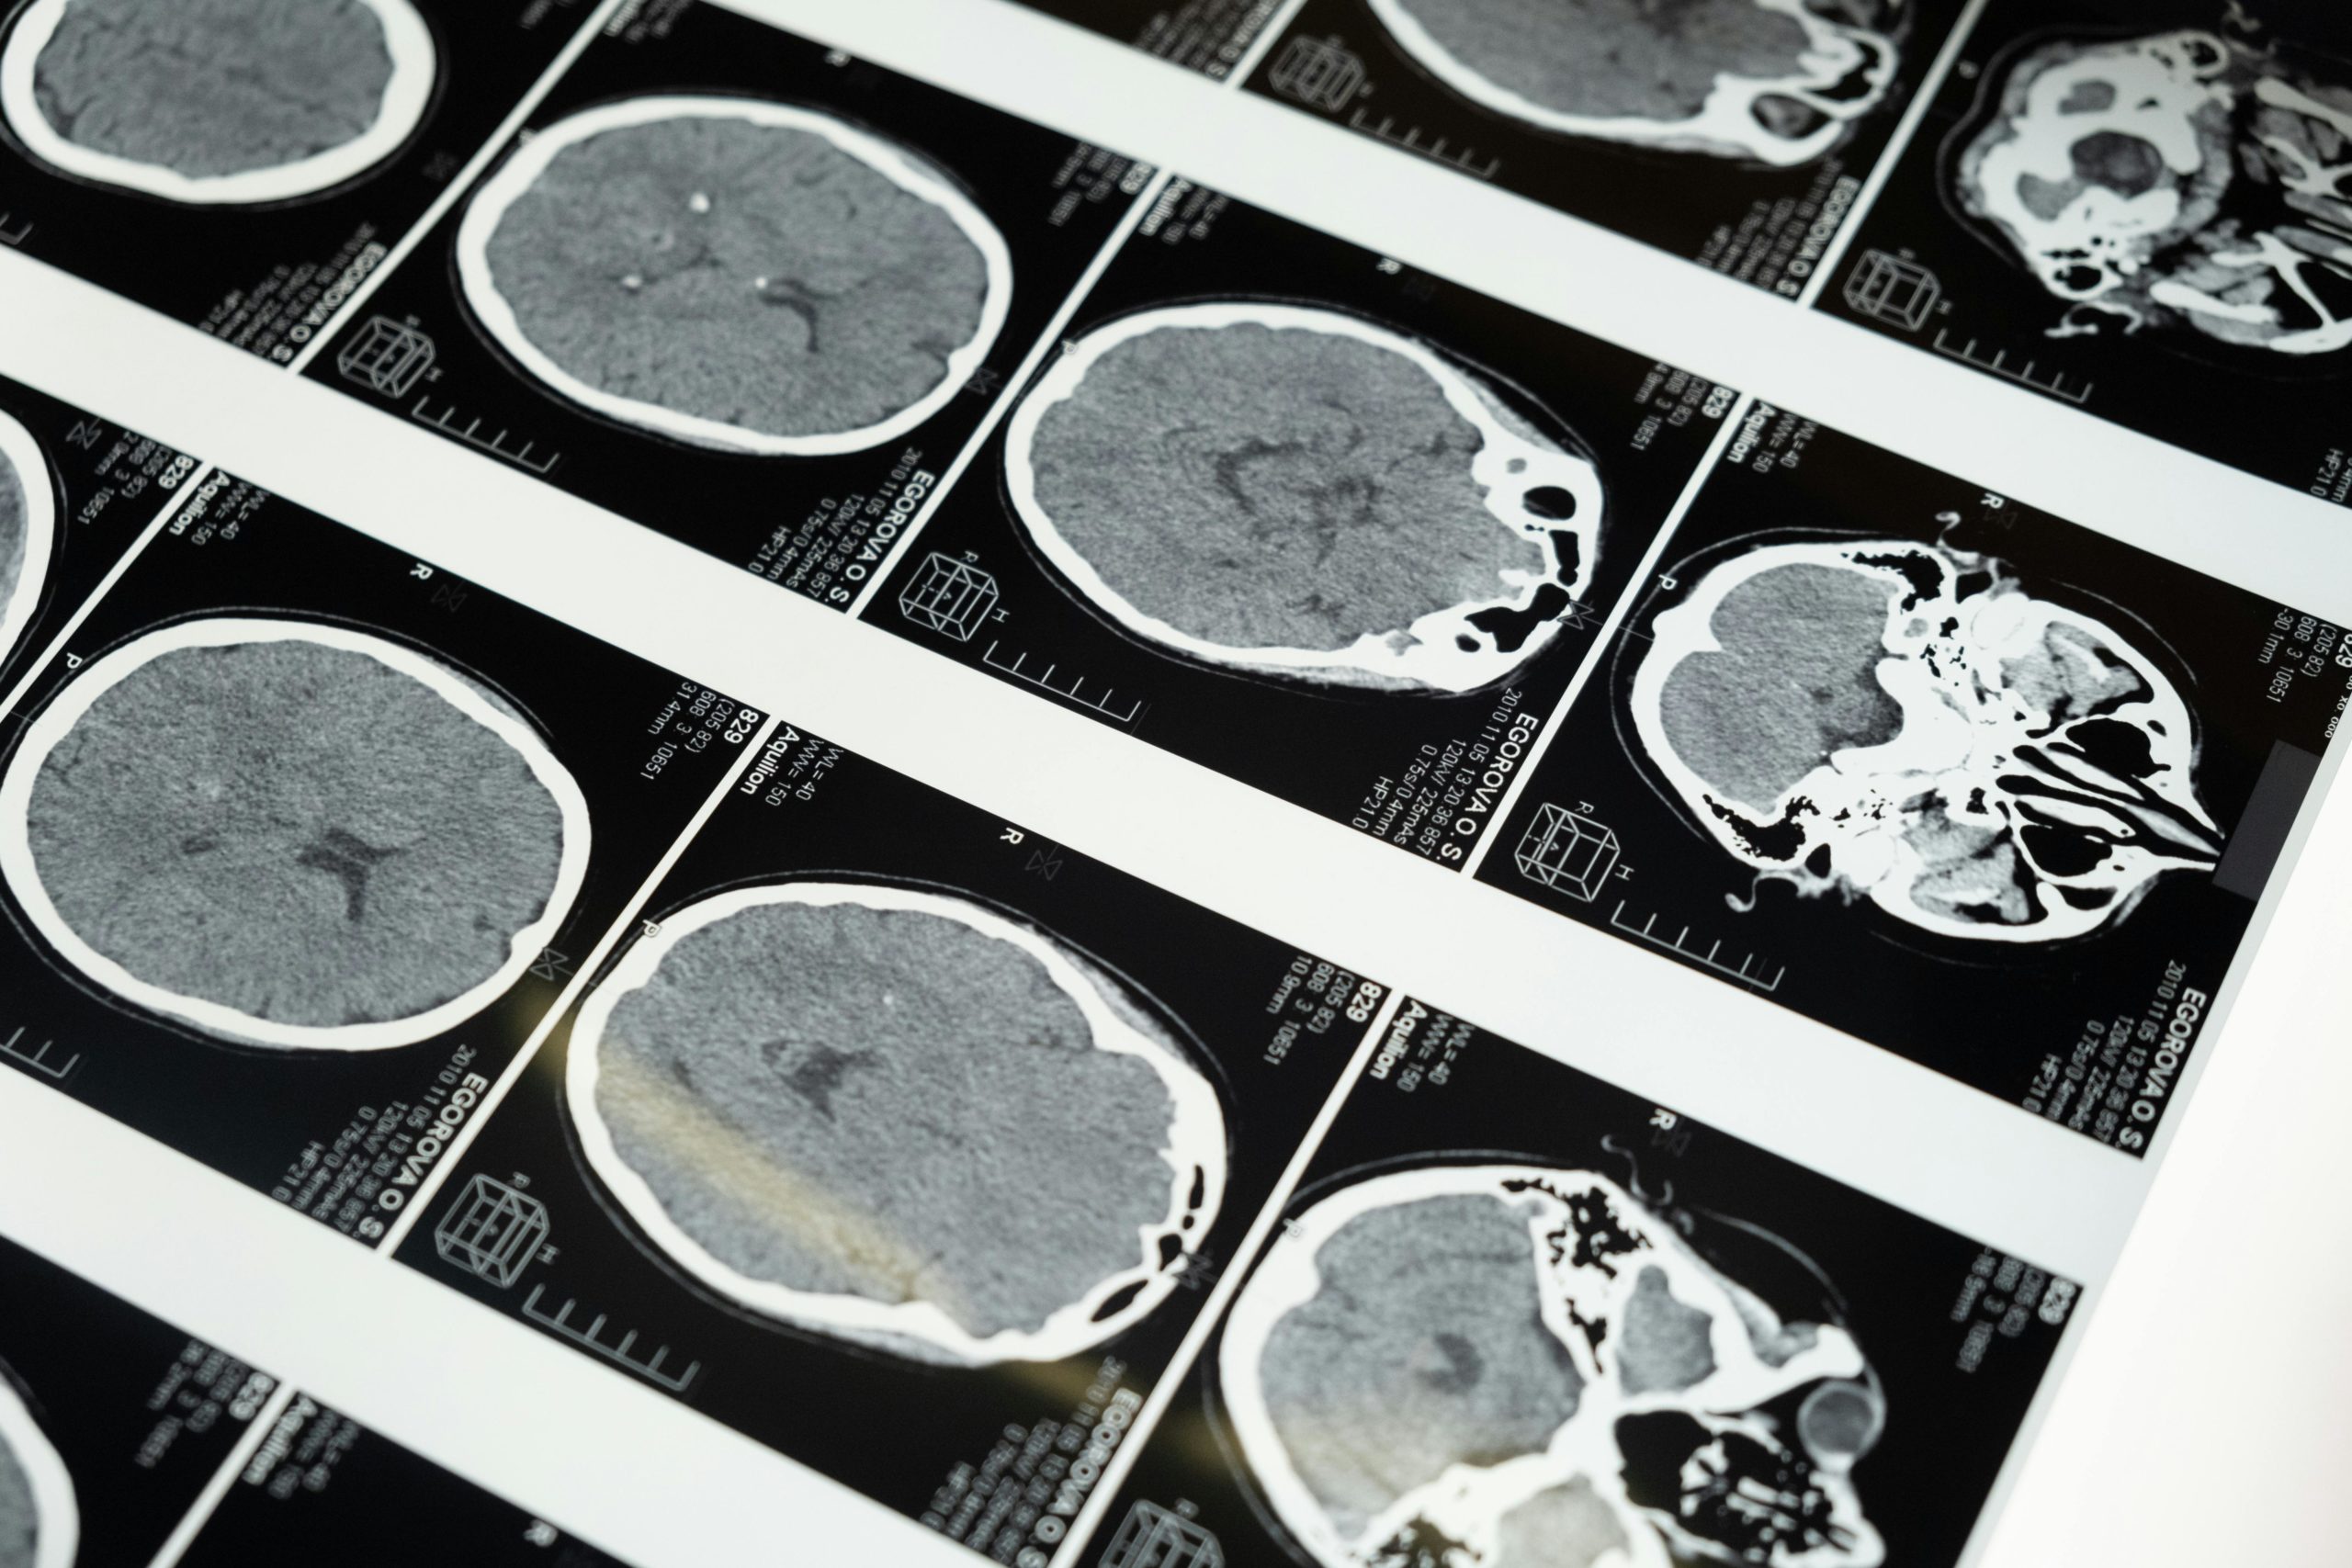

Gehirnforscher nutzen verschiedene Methoden, um im lebenden Menschen Einsicht in die Hirnaktivität zu gewinnen. Die wichtigsten Verfahren sind bildgebende Neuroimaging-Methoden und das EEG.

• MRT (Magnetresonanztomografie): Mit dem MRT können Forscher die Struktur und teilweise auch die Aktivität des Gehirns messen. Normale MRT-Bilder zeigen z. B. das Volumen von Hirnarealen oder bestimmen, ob die Anatomie normal ist. In der Lernforschung verwendet man vor allem das fMRT (funktionelle MRT). Dabei bleibt die Person in einer Röhre liegen und löst Aufgaben, während das Gerät Blutfluss und Sauerstoffverbrauch misst. Aktive Hirnregionen „leuchten“ dadurch in den Bildern auf.

• PET (Positronen-Emissions-Tomografie): Hierfür injiziert man eine schwach radioaktive Substanz, die sich im Blut verteilt und vor allem in besonders aktiven Hirnarealen anreichert. Die Messung zeigt dann eine Art „Karte“ der Gehirnaktivität. Ein Vorteil ist, dass bestimmte Stoffwechselvorgänge sichtbar werden. Allerdings ist PET aufwendiger und kommt seltener in der Lernforschung zum Einsatz.

Diese Forschungsmethoden haben bereits viele Überraschungen geliefert. So fanden Hirnforscher heraus, dass beim Erlernen eines Instruments wie Geige bestimmte Hirnareale wachsen oder stärker verknüpft werden. Eine Grundaussage lautet: Lernen verändert das Gehirn – und mit diesen Methoden können Wissenschaftler diese Veränderungen sichtbar machen.